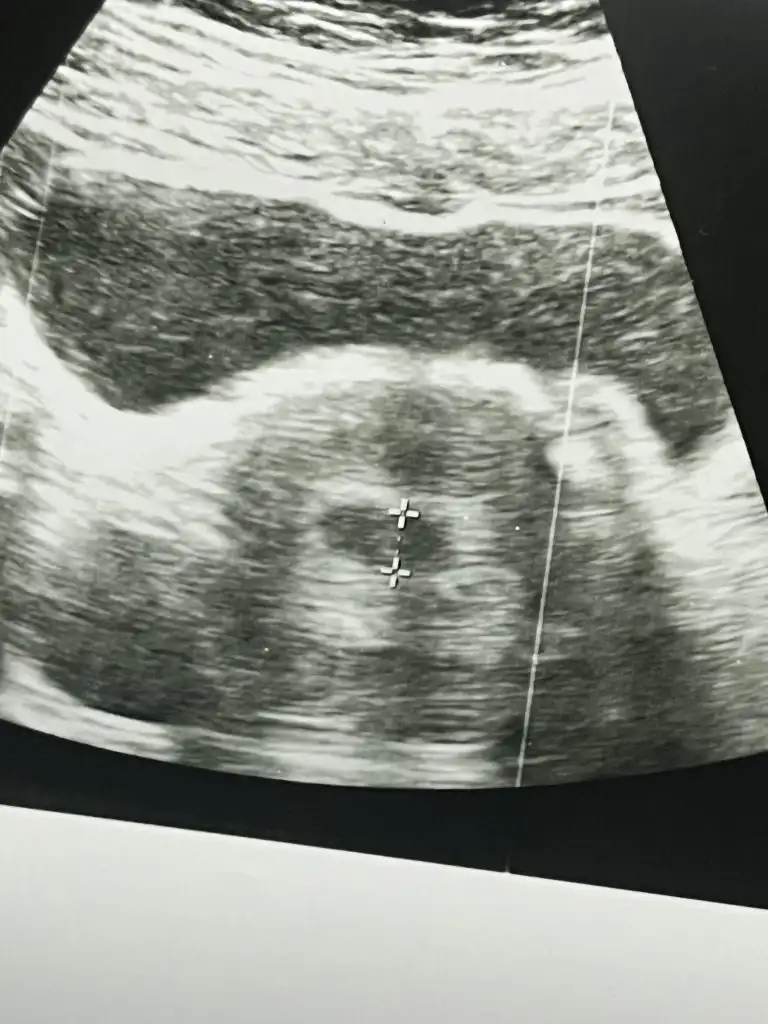

Sanırım belirli binli sayılarda belli bir sayıdan sonra %30 artış da normal diye okudum.Kızlar bugün 5+1 oldum. En son 8 ocakta beta baktırdım, 836 çıkmıştı. Cuma günü Vajinal ultrason ile kese göründü. Doktorum bugün kontrole çağırdı ve tekrar beta istedi. Karindan kesemizi gördük bugün. Haftasıyla uyumlu dedi. Ama beta hcg 9054 geldi. Normal mi bu iki kattan fazla artmış olması kötüye işaret değildir dimi ?

nolmuş birden öyle şahlanmış maşallahKızlar bugün 5+1 oldum. En son 8 ocakta beta baktırdım, 836 çıkmıştı. Cuma günü Vajinal ultrason ile kese göründü. Doktorum bugün kontrole çağırdı ve tekrar beta istedi. Karindan kesemizi gördük bugün. Haftasıyla uyumlu dedi. Ama beta hcg 9054 geldi. Normal mi bu iki kattan fazla artmış olması kötüye işaret değildir dimi ?

Hayırlı olsun canımm ben bugün 5+4 te kese gördüm ama kalp atışı için 30 ocakta gel dediKızlar herkese selam, ben de tüp bebek ile hamileyim, bu 2. Gebeliğim 8 yaşında oğlum var ama çok zaman geçti unutmuşum her şeyibugün 5+0 günümdeyim 5+4 de doktora kontrole gideceğim, sizce kalp atışı duyulur mu?